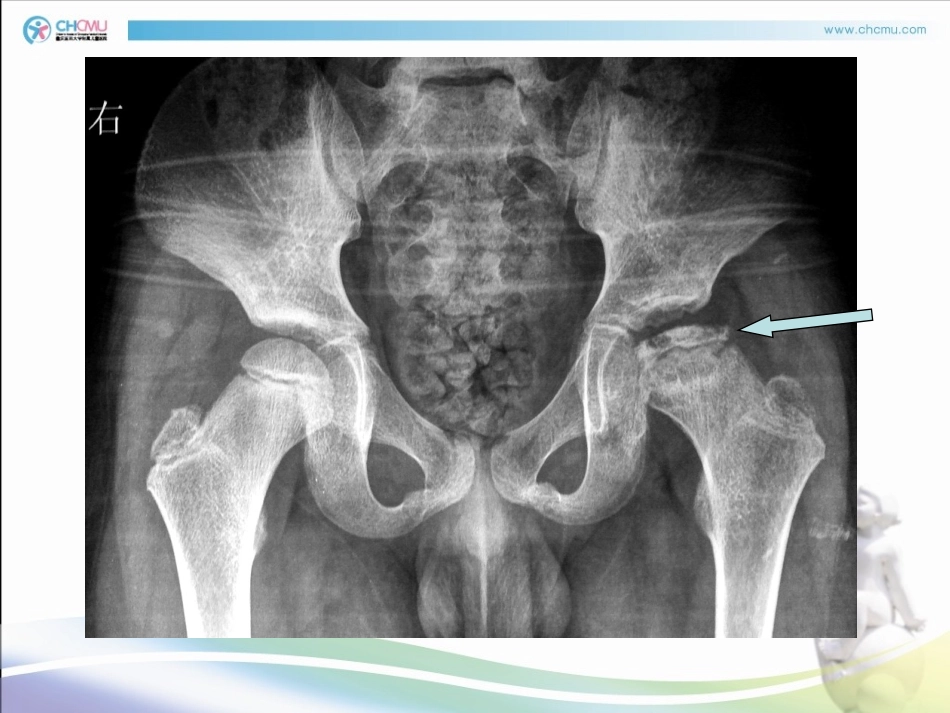

((Legg-Calvé-PerthesLegg-Calvé-Perthes病)病)重庆医科大学儿科学院外科教研室宿玉玺副主任医师、副教授教师简介教师简介SuYuxi宿玉玺骨科中心二病房副主任医师、副教授Email:yuxisu@163.com掌握:病理及X线表现、临床表现及体征早期诊断、治疗原则了解:Catterall分型及意义、治疗方法、鉴别诊断难点:病因、病理及X线表现命名:儿童股骨头缺血性坏死、儿童股骨头无菌性坏死、股骨头(幼年变形性)骨软骨炎(病)、扁平髋、巨髋症、Legg病、Legg-perthes病、Legg-calvé-perthes病(LCP)。习惯简称--Perthes病一、历史与命名1910年分别由Legg(美)Calvé(法)Perthes(德)描述了本病。起病隐匿,自然病程长(2-3年)男孩多见,男:女=4:14-8岁儿童多见单侧多见(双侧约10%)世界各地发病率不相同(约1‰)二、概述股骨头骨骺缺血性坏死引起的疾病确切致病原因目前尚不清楚㈠血供因素研究发现儿童股骨头营养血管在解剖上存在缺陷或异常:4-8岁儿童圆韧带动脉尚未参与股骨头血供,干骺端动脉(来自旋股内侧动脉)有骺板阻隔不能在骨内形成吻合支,骺外侧动脉成为唯一男孩好发的另一种解释:好动,损伤机会多,反复微损伤,损伤敏感性三、病因1948年Chandlen提出血管栓塞因素,称本病系“髋关节冠状血管疾病”1973年Kemp幼犬动物模型(髋关节囊内压力↑>150mmHg→网状血管阻塞,血供障碍)1982-1983年Green、国内马承宣提出股骨上段骨髓内压增高→关节囊静脉淤血梗阻1987年刘尚礼博士研究证实有髋关节周围静脉有瘀血改变、压力增高㈡血管因素(分动脉或静脉)㈢发育障碍许多学者认为Perthes病是一全身性骨骼发育异常的疾患,股骨头缺血坏死仅为该病的局部表现。如有人报道Perthes病同时伴有其他部位的先天性畸形Ponseti发现骨骺软骨增厚及骺结构紊乱有研究发现单侧患儿健侧骺软骨有异常㈣凝血功能异常血液中C蛋白或S蛋白缺乏或抑制C蛋白活性可导致静脉栓塞、髓内高压。本病有一定的家族史(在5代谱系中的63人中有28人患此病)被动吸烟、内分泌变化、代谢性疾病等有关患病期,骨龄普遍性延迟免疫功能紊乱:1976年Neveloes报道患儿血中的IgG明显升高与人类种族和环境的关系:①黑种人群儿童患本病少②欧美地区为本病高发,非洲报告少股骨头缺血性坏死为系全身性疾患的局部表现之一㈤其他㈤㈤其他其他早期Legg等均认为是一种感染疾患,但未得到病原菌证实一些学者提出该病与髋关节暂时性滑膜炎关系密切,统计髋关节暂时性滑膜炎中0.5~10%以后会发生股骨头坏死病理研究显示Perthes病是骨骺多次缺血性梗死的结果,表现在同一病灶中既有骨坏死又有骨修复再生。此特点不同于其它骨坏死疾患,故是儿童特有。四、病理及X线表现关节囊影增宽,关节间隙增宽,股骨头外移,骨骼高度无变化初期或滑膜炎或渗出期初期或滑膜炎或渗出期(1(1--44周周))第一期第一期关节中滑膜和关节囊水肿、充血、关节液渗出↑,关节压↑。骨质脱钙,骨质疏松X线X线病理X线X线主要是骨髓的坏死,骨小梁片、点状坏死,骨细胞核消失,坏死团内偶见残存骨组织,无再生迹象股骨头骨骺密度加深,无透亮区,骺外侧开始出现扁平,干骺端开始增宽及囊性变缺血期或坏死期缺血期或坏死期((数月-数月-11年年))病理第二期第二期X线X线股骨头全部扁平,分裂呈小块,股骨颈增宽,囊性变和骨质疏松明显骨小梁碎片开始吸收,新生血管及肉芽进入,有不成熟的新生骨组织替代碎裂期或恢复期(1-3年)病理第三期第三期第三期第三期X线X线骨片吸收完成,新生骨大量出现,吸收坏死骨及再生完成1/3病例可完全康复2/3病例残留不同程度的巨髋畸形愈合期或残余期骺逐渐生长、增厚、透亮区消失并密度渐正常,出现正常骨小梁,但多有头扁平、蕈状畸形、半脱位、驼峰征、颈短宽伴大粗隆高位。病理第四第四期第四第四期X线分型及意义1.Catterall分型2.Herring分型3.Salter-Thompson分型1.Catterall(1971)分型Ⅰ型仅仅是股骨头前部受累,无干骺端变化Ⅱ型50%股骨头前外侧受累,内外侧柱未受累(中心出现V形透亮区)Ⅲ型75%股骨头前外侧受累(成为死骨),仅内侧不受累,广泛干骺端反应(...